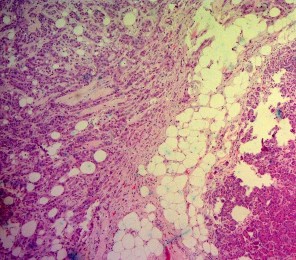

Ảnh 5. Bệnh phẩm khối tá tụy | Ảnh 6. Tế bào học: UTBMT ống tụy. Mã số SR0125, nhuộm H&Ex50 |

Ảnh 7. Tế bào học: UTBMT ống tụy. Mã số SR0125, nhuộm H&E x 100 | Ảnh 8. Tế bào học: UTBMT ống tụy. Mã số SR0125, nhuộm H&E x 100 |